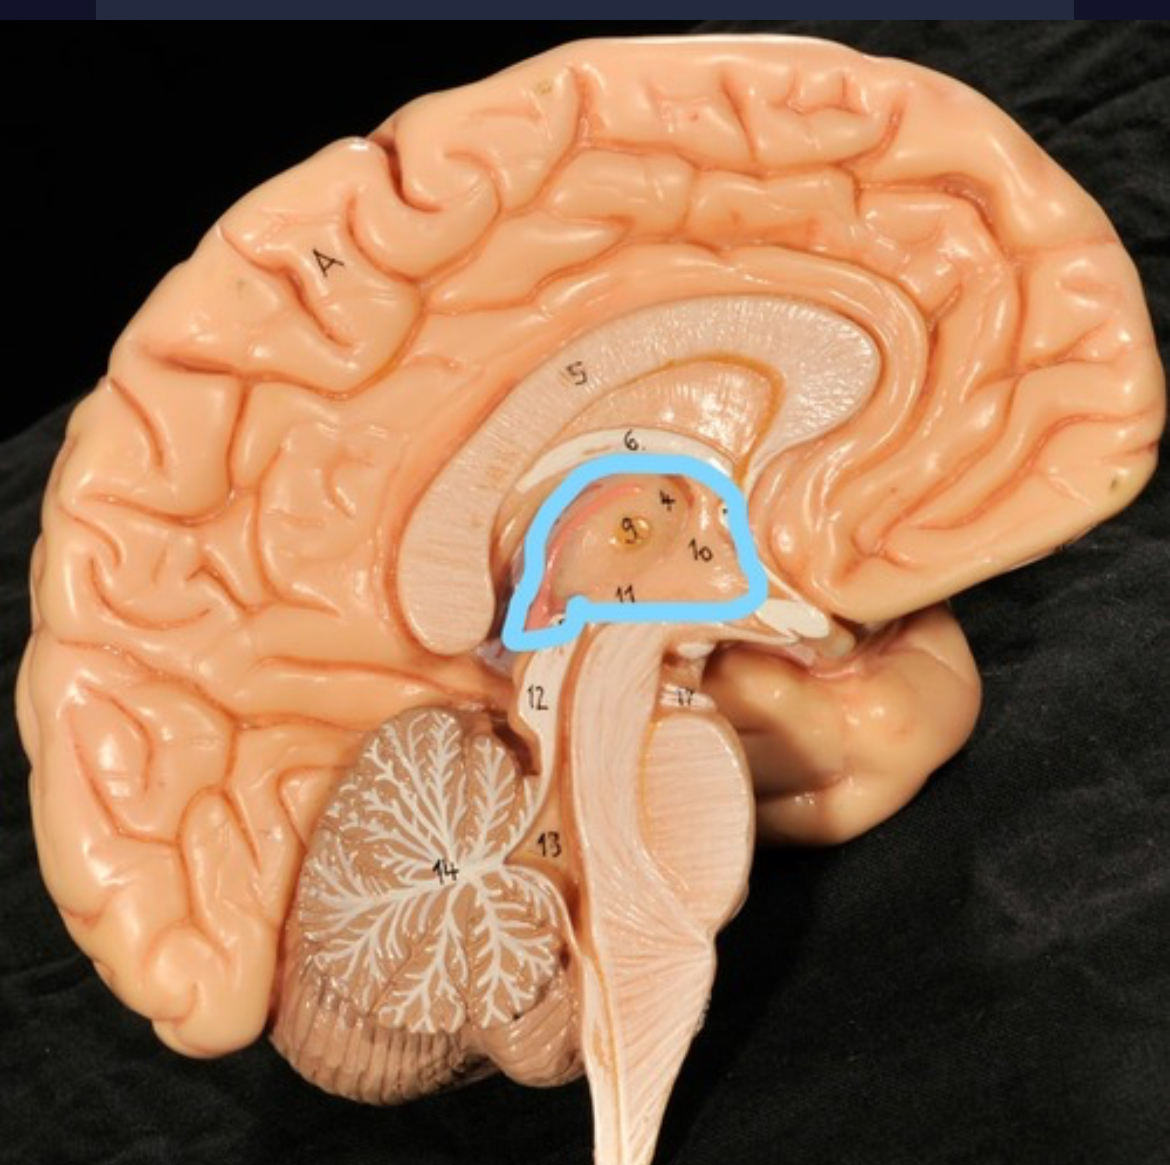

Diencephalon

Thalamus

3rd ventricle

Hypothalamus

Epithalamus (pink line)

Choroid plexus of 3rd ventricle

Cerebral aqueduct (midrain)

4th ventricle

central canal